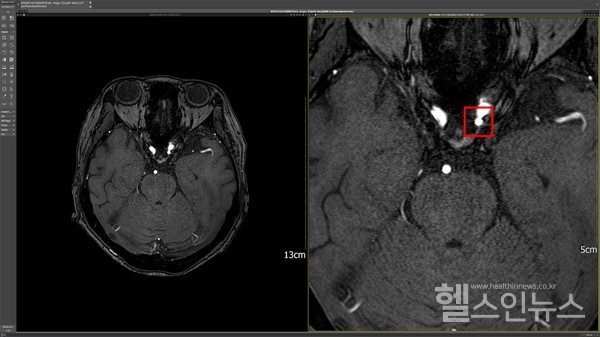

해당 솔루션은 현재 국내 17개 상급병원에 설치돼 있다. 뇌 MRA 검사 시, 환자의 동의만 있다면 DEEP:NEURO(딥뉴로)를 통해 뇌동맥류 검출을 보조 받을 수 있으며, 자사는 적용 건당 병원에 비용을 청구하게 된다.